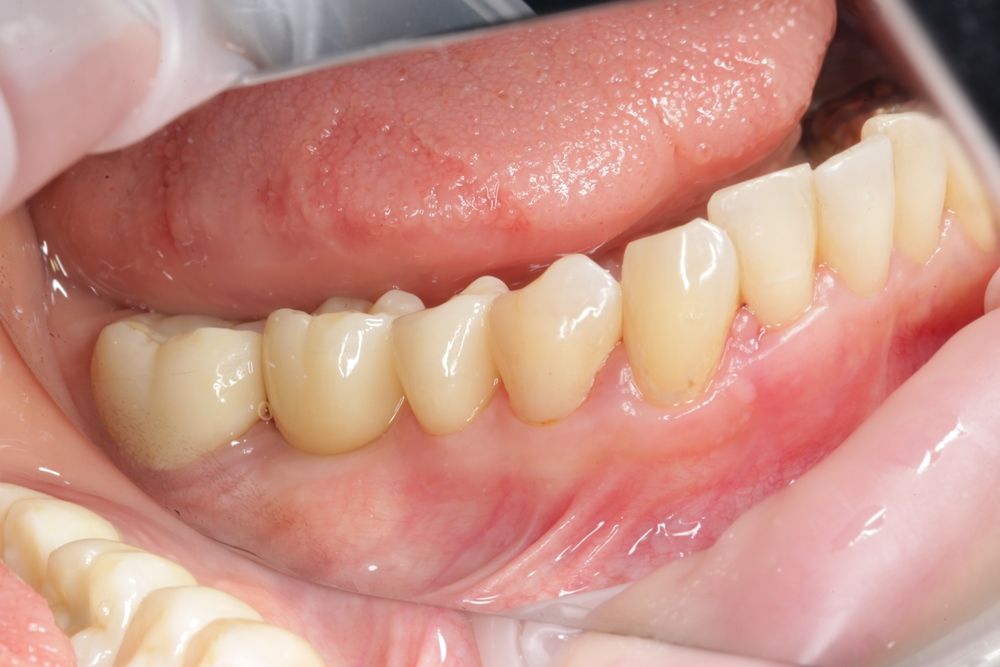

Имплантация жевательных зубов,

это самая востребованная операция.

Анна Анатольевна Кушнарева

хирург - имплантолог

фото коронок